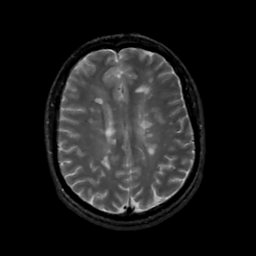

MR Study #14, June 2, 1991 -- Slice #33

[Home][Help][Clinical][Tour 1][Tour 2] Slice 33